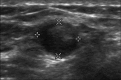

Figure 2.

Sonographic image of the left breast demonstrates a 7 × 6 mm mixed echogenicity ovoid mass at the 2:00 position, approximately 10 cm from the nipple. Histologic sampling yielded findings consistent with a metastatic lymph node from an occult breast primary.